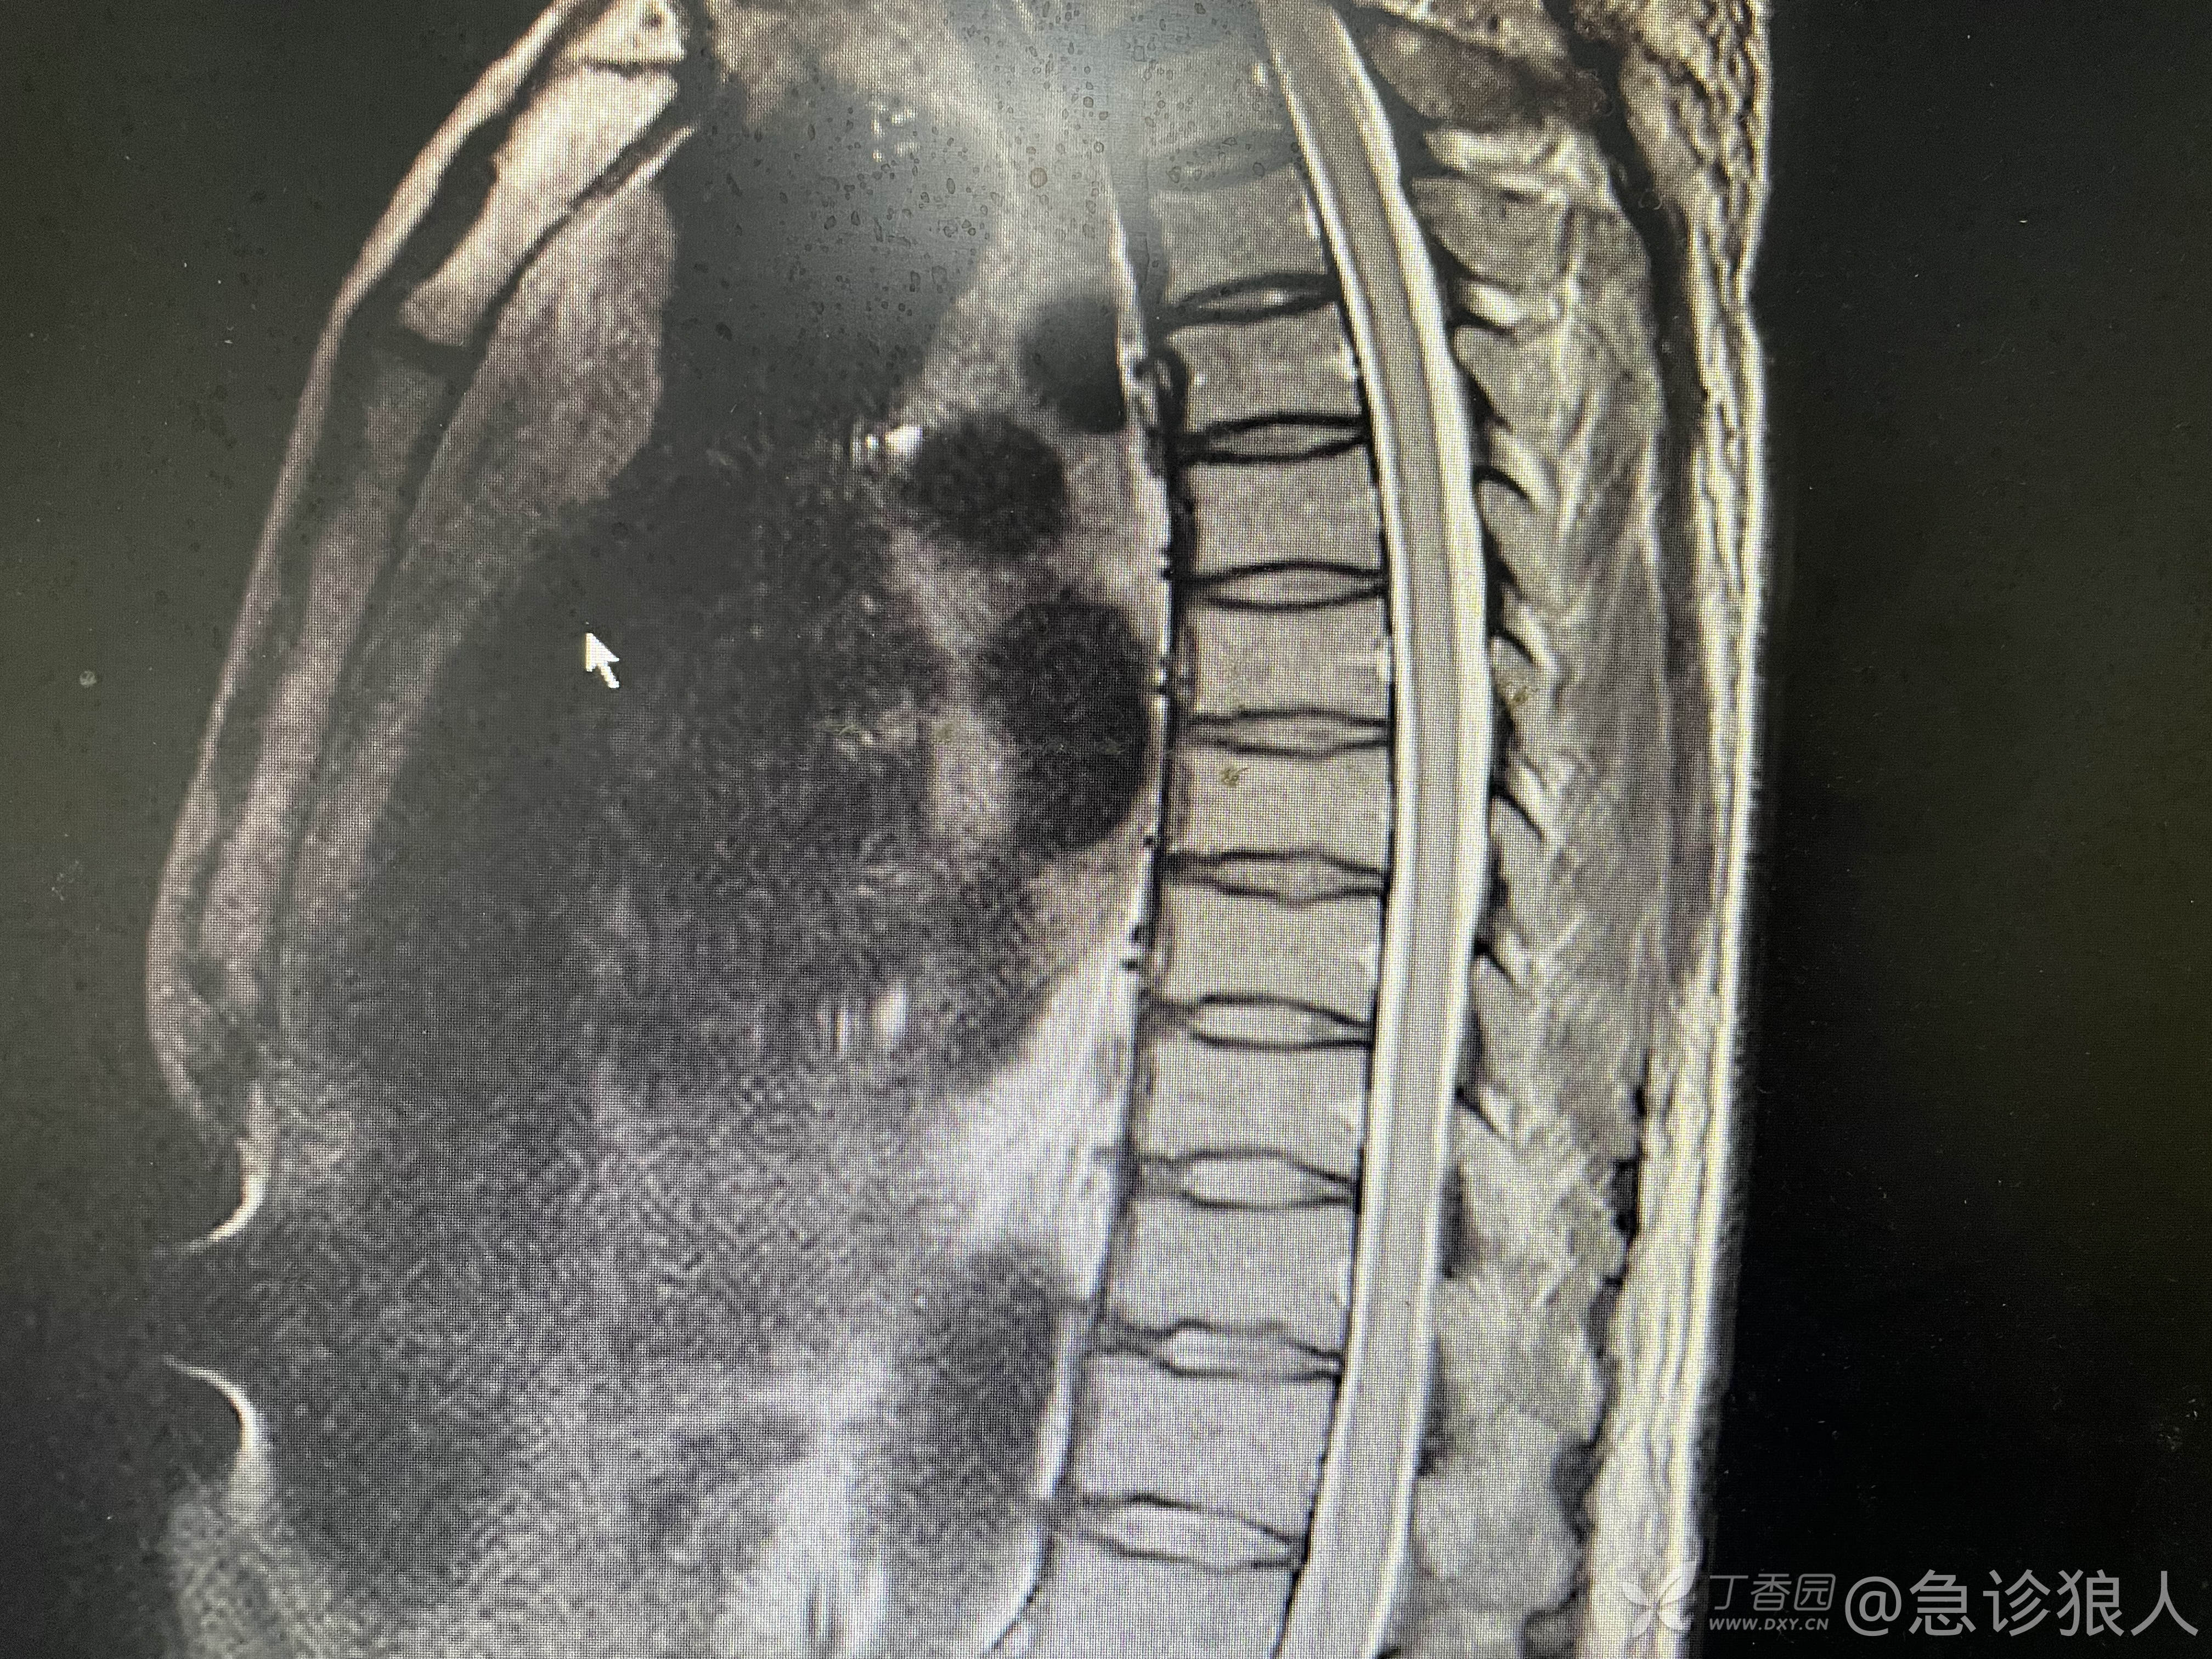

磁共振强化如下:

脑脊液培养阴性!无菌性脊髓炎!

看不懂磁共振,只能读懂结论,查了文献,应该确诊狼疮脑没问题!已加用激素冲击、环磷酰胺,患者现在明显好转!